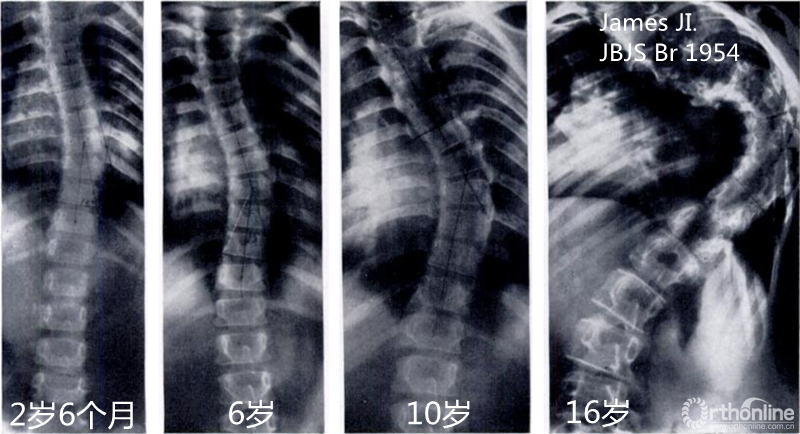

脊柱侧凸在青春期迅速进展(Scott JC, Morgan TH. JBJS Br 1955)